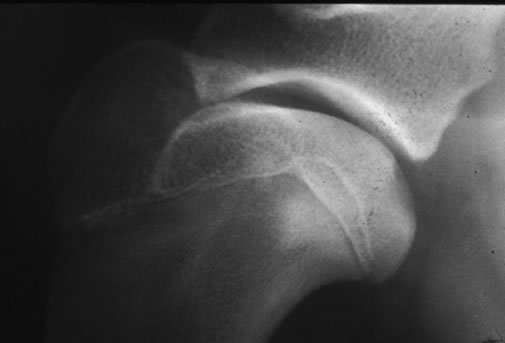

肩関節脱臼

肩関節脱臼とは

肩関節が外れた状態、内方脱臼と外方脱臼があります。

レントゲン検査

手術をせずに整復し固定をおこなっても治ることが少なく、外科的に脱臼を整復し固定する必要がある場合が多いです。内方脱臼ではスーチャーアンカーを用いて整復する方法など、外方脱臼では二頭筋腱の転移術などを行います。それでも再脱臼する場合、最終的な救済処置として関節固定術を行うこともあります。